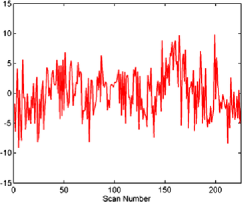

The subject in Figure 3 seems to exhibit strong deviations from stationarity—in fact, the -value associated with this subject is below based on the bootstrap test given in Section 7. It should be stressed that the change detection is a global hypothesis test combined over all components considered. In this way, while taking more components will help increase the chance that the change is present in one, it will come at the cost of the size of the change needed in finite samples for an omnibus test of this type. However, the subject shown in the figure did cause a rejection of the null hypothesis of no change both in the 64 and 125 subspace size omnibus tests. While the pictures in Figure 3 indicate that an epidemic change is indeed a good first approximation for the nonstationarities occurring for this particular subject, more deviation (maybe more change-points) does seem to be present. In Figure 4, a second subject is shown with a much smaller deviation from stationarity (most of the components seem to have little to no possible mean change present), which is significant but does not survive the false discovery rate (FDR) correction (see Section 4.3).

Figures 5–7 show three component time series selected for their different properties. The component in Figure 5 can be seen to be a candidate series for a change to have occurred with the resulting change corrected series visually appearing much more stationary (although it is likely there are other nonstationarities present as well). This series, from subject 01018 in the connectome data set, was found to have evidence of nonstationarities when the sample version of the statistic (given in Section 6.2) was tested on both a 64 and 125 component projection.